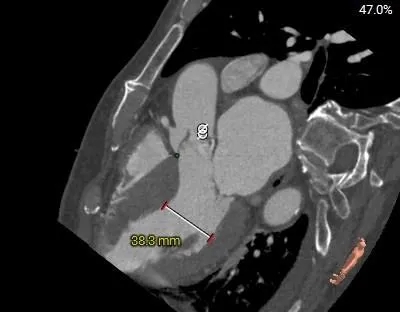

Left Coronary

12.1mm

LCA & Leaflet

12.7mm<15.8mm

Right Coronary

17.1mm

RCA & Leaflet

16.3mm<19.4mm

-

双侧冠脉开口高度可

左、右冠瓣叶长度>冠脉开口下缘到根部距离

结合SOV、STJ测量,窦部空间较小,预估冠脉阻挡风险较高

收缩期测量心室腔稍大

心室壁厚度尚可

钙化积分测量达1546mm3

极重度钙化,左窦、无窦钙化较重

外周入路条件可